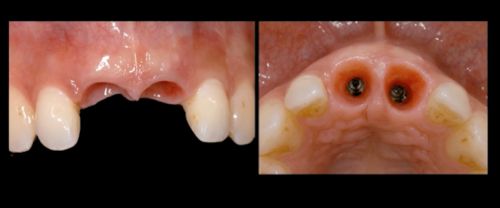

Фото. Большой вертикальный дефект на месте удаленных зубов.

Фото. Удаление 11, 21 зубов из-за большой потери твердых тканей зубов.

· ширина и высота кости и мягких тканей (чем больше дефект, тем сложнее создать эстетическую работу).